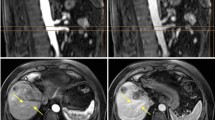

Quantitative segmentation results from manual segmentation and neural network segmentation are illustrated in a representative case in Fig. 4, showing an excellent performance of liver parenchymal segmentation and a good delineation and differentiation between the portal and hepatic veins. The neural network trained with the single-modal in-phase reconstruction achieved the highest overall performance with an average DSC of 0.936 ± 0.02 for liver parenchyma, 0.634 ± 0.09 for portal veins, and 0.532 ± 0.12 for hepatic veins, as shown in Table 3. All single- and multi-modal inputs yielded comparable liver parenchyma segmentations without statistically significant differences (p = 0.09). In contrast, performance of the portal and hepatic veins segmentation was significantly lower when using the opposed-phase, as compared to the in-phase single-modal input (p < 0.001), while there was no significant difference between the in-phase and water-reconstruction input for portal (p = 0.331) and hepatic veins (p = 1.0) in the post hoc comparison (Table 4). There was no significant difference for liver, portal, and hepatic vessel segmentation between the in-phase single-modal input and the multi-modal input combining in-phase with opposed phase, fat, and water reconstructions (Fig. 5). Similar results were obtained by using the average precision metric, ignoring the true negative background outside of the liver in the MRI field of view, as demonstrated by the precision-recall curves in Fig. 6.

Example of an expert (first column) and automated (second column) segmentation of liver parenchyma (red), portal veins (purple), and hepatic veins (blue). The third column shows a visualization of the correct segmentation, as well as under-segmentation (cyan), and over-segmentation (yellow), as performed by the model with an in-phase sequence.